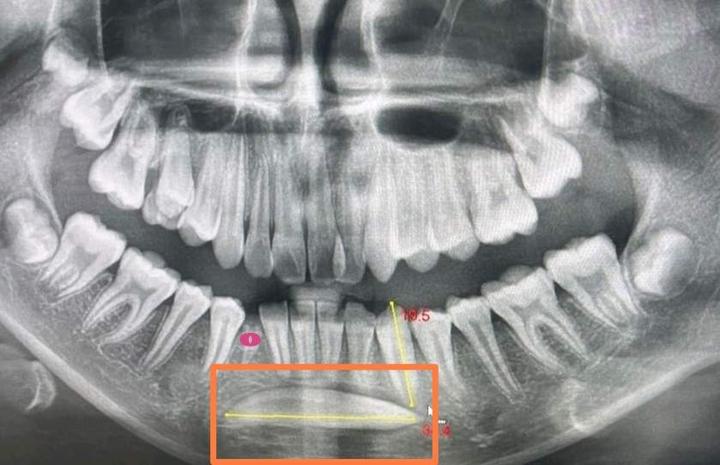

下面三个病例都是因为乳牙龋齿,乳牙滞留,导致对应恒牙阻生。特别提醒:1.重视乳牙龋齿的防治。2.换牙期间6——12岁至少每半年口腔检查一次,及时发现换牙异常,及时干预。

红点处是龋齿滞留的乳牙,方框里是埋伏阻生的恒牙。